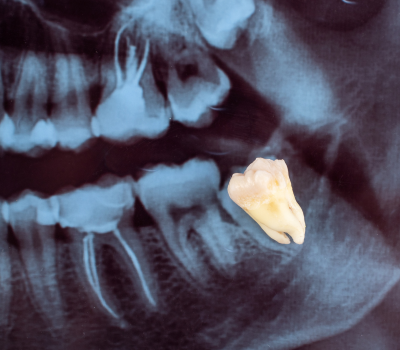

Wisdom teeth, also known as third molars, are the last set of teeth to emerge, typically between the ages of 17 and 25. While some individuals have no issues with their wisdom teeth, many experience complications due to lack of space, improper alignment, or impaction. When these teeth grow at the wrong angle or remain trapped beneath the gums, they can lead to severe pain, swelling, infection, and even damage to surrounding teeth. At Gentle Dental Clinic, we specialize in safe and minimally invasive wisdom tooth extraction, ensuring a smooth, pain-free experience that protects long-term oral health. Whether your wisdom teeth are causing discomfort now or have the potential to create problems in the future, our expert dental team provides personalized care and advanced surgical techniques to ensure a quick recovery and long-lasting results.

Not all wisdom teeth require removal, but when they cause issues, prompt extraction is the best way to prevent ongoing pain and complications. Common signs that indicate the need for removal include persistent jaw pain, swelling in the gums, difficulty opening the mouth fully, frequent infections, or pressure against adjacent teeth. In some cases, wisdom teeth can contribute to crowding, shifting of other teeth, or cyst formation, which can compromise the health of the jawbone. Our dental specialists at Gentle Dental Clinic carefully assess X-rays and oral examinations to determine whether extraction is necessary. By addressing these issues early, we help patients avoid future discomfort and expensive restorative treatments.

At Gentle Dental Clinic, we prioritize patient comfort and advanced surgical precision to make the wisdom tooth extraction process as stress-free as possible. The procedure begins with a detailed consultation and imaging scans to evaluate the position of the wisdom teeth and identify any risks. On the day of the extraction, we use local anesthesia or sedation options to ensure a completely painless experience. If the wisdom tooth is impacted, our skilled surgeons carefully remove small sections of bone or gum tissue to access the tooth without unnecessary trauma. Our advanced techniques help minimize bleeding, reduce swelling, and promote faster healing, allowing patients to recover comfortably. With our expert approach and state-of-the-art tools, we ensure that every extraction is efficient, precise, and safe.

Wisdom teeth may need extraction if they cause pain, swelling, infections, or pressure on surrounding teeth. If they are impacted, misaligned, or difficult to clean, removal is often recommended to prevent future complications. A dental exam and X-ray can help determine if extraction is necessary.